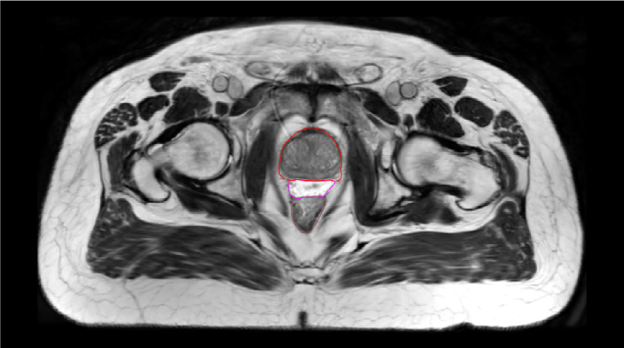

SpaceOAR-CT image.

A. SpaceOAR-CT

SpaceOAR-T2 MRI image.

B. SpaceOAR-T2 MRI

SpaceOAR Vue-CT image.

C. SpaceOAR Vue-CT

SpaceOAR Vue-T2 MRI image.

D. SpaceOAR Vue-T2 MRI

Figure 1. SpaceOAR Hydrogel vs. SpaceOAR Vue Hydrogel on CT and 1.5T T2 MRI simulation scans. Representative axial CT and T2 MRI simulation scan images from two patients who received perirectal hydrogel spacer with SpaceOAR Hydrogel (A, B) or SpaceOAR Vue Hydrogel (C, D). For SpaceOAR Hydrogel (A, B) hydrogel was contoured on MRI and modified based on CT, whereas for SpaceOAR Vue Hydrogel (C, D) hydrogel was contoured directly on the CT simulation scan. Note that for SpaceOAR Hydrogel (A, B) the T2 MRI hyperintense region in B between the prostate and rectal contours is not easily seen on CT in A. For SpaceOAR Vue Hydrogel, the hyperintense region on the T2 MRI in D corresponds to the hyperdense region between the prostate and rectum on CT in C. Red- prostate contour, Magenta- hydrogel contour, Brown- rectal contour.